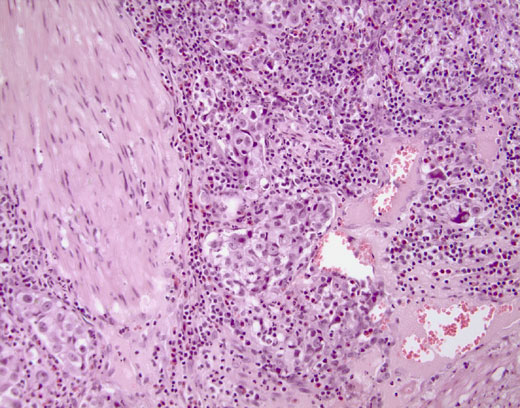

Cross-section #22 - 20X

click on the slide photo to see 40X magnification